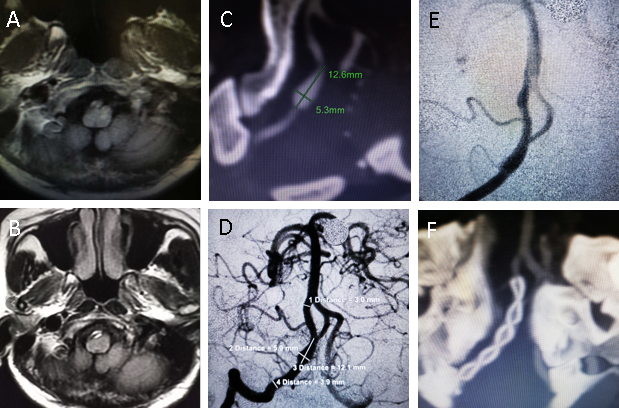

近日,平昌县人民医院神经内科收治了一名因“反复头昏头痛 2 年,加重 1 天”入院的 41 岁女性患者。经过头颅MRI和CTA检查确诊为右侧颅内椎动脉夹层动脉瘤(5.3mm*12.6mm)合并开窗畸形。为降低病变扩大和破裂的风险,彻底治愈本病,我院卒中团队决定为患者进行血流导向装置植入术。

手术由海军军医大学附属长海医院神经外科赵开军教授和平昌县人民医院卒中团队的刘军胜和何天称主治医师一起完成,血流导向装置选用上海微创公司的国产血流导向装置 Tubridge。手术人员对动脉瘤的大小、载瘤动脉的直径以及支架预覆盖的长度进行了精准测量后,将大小合适的支架精准释放于预先规划的位置,充分覆盖病变区,载瘤动脉和分支血管均保持通畅,支架打开良好。整个手过程顺利。术后,患者在卒中中心护理团队的护理下,恢复良好。